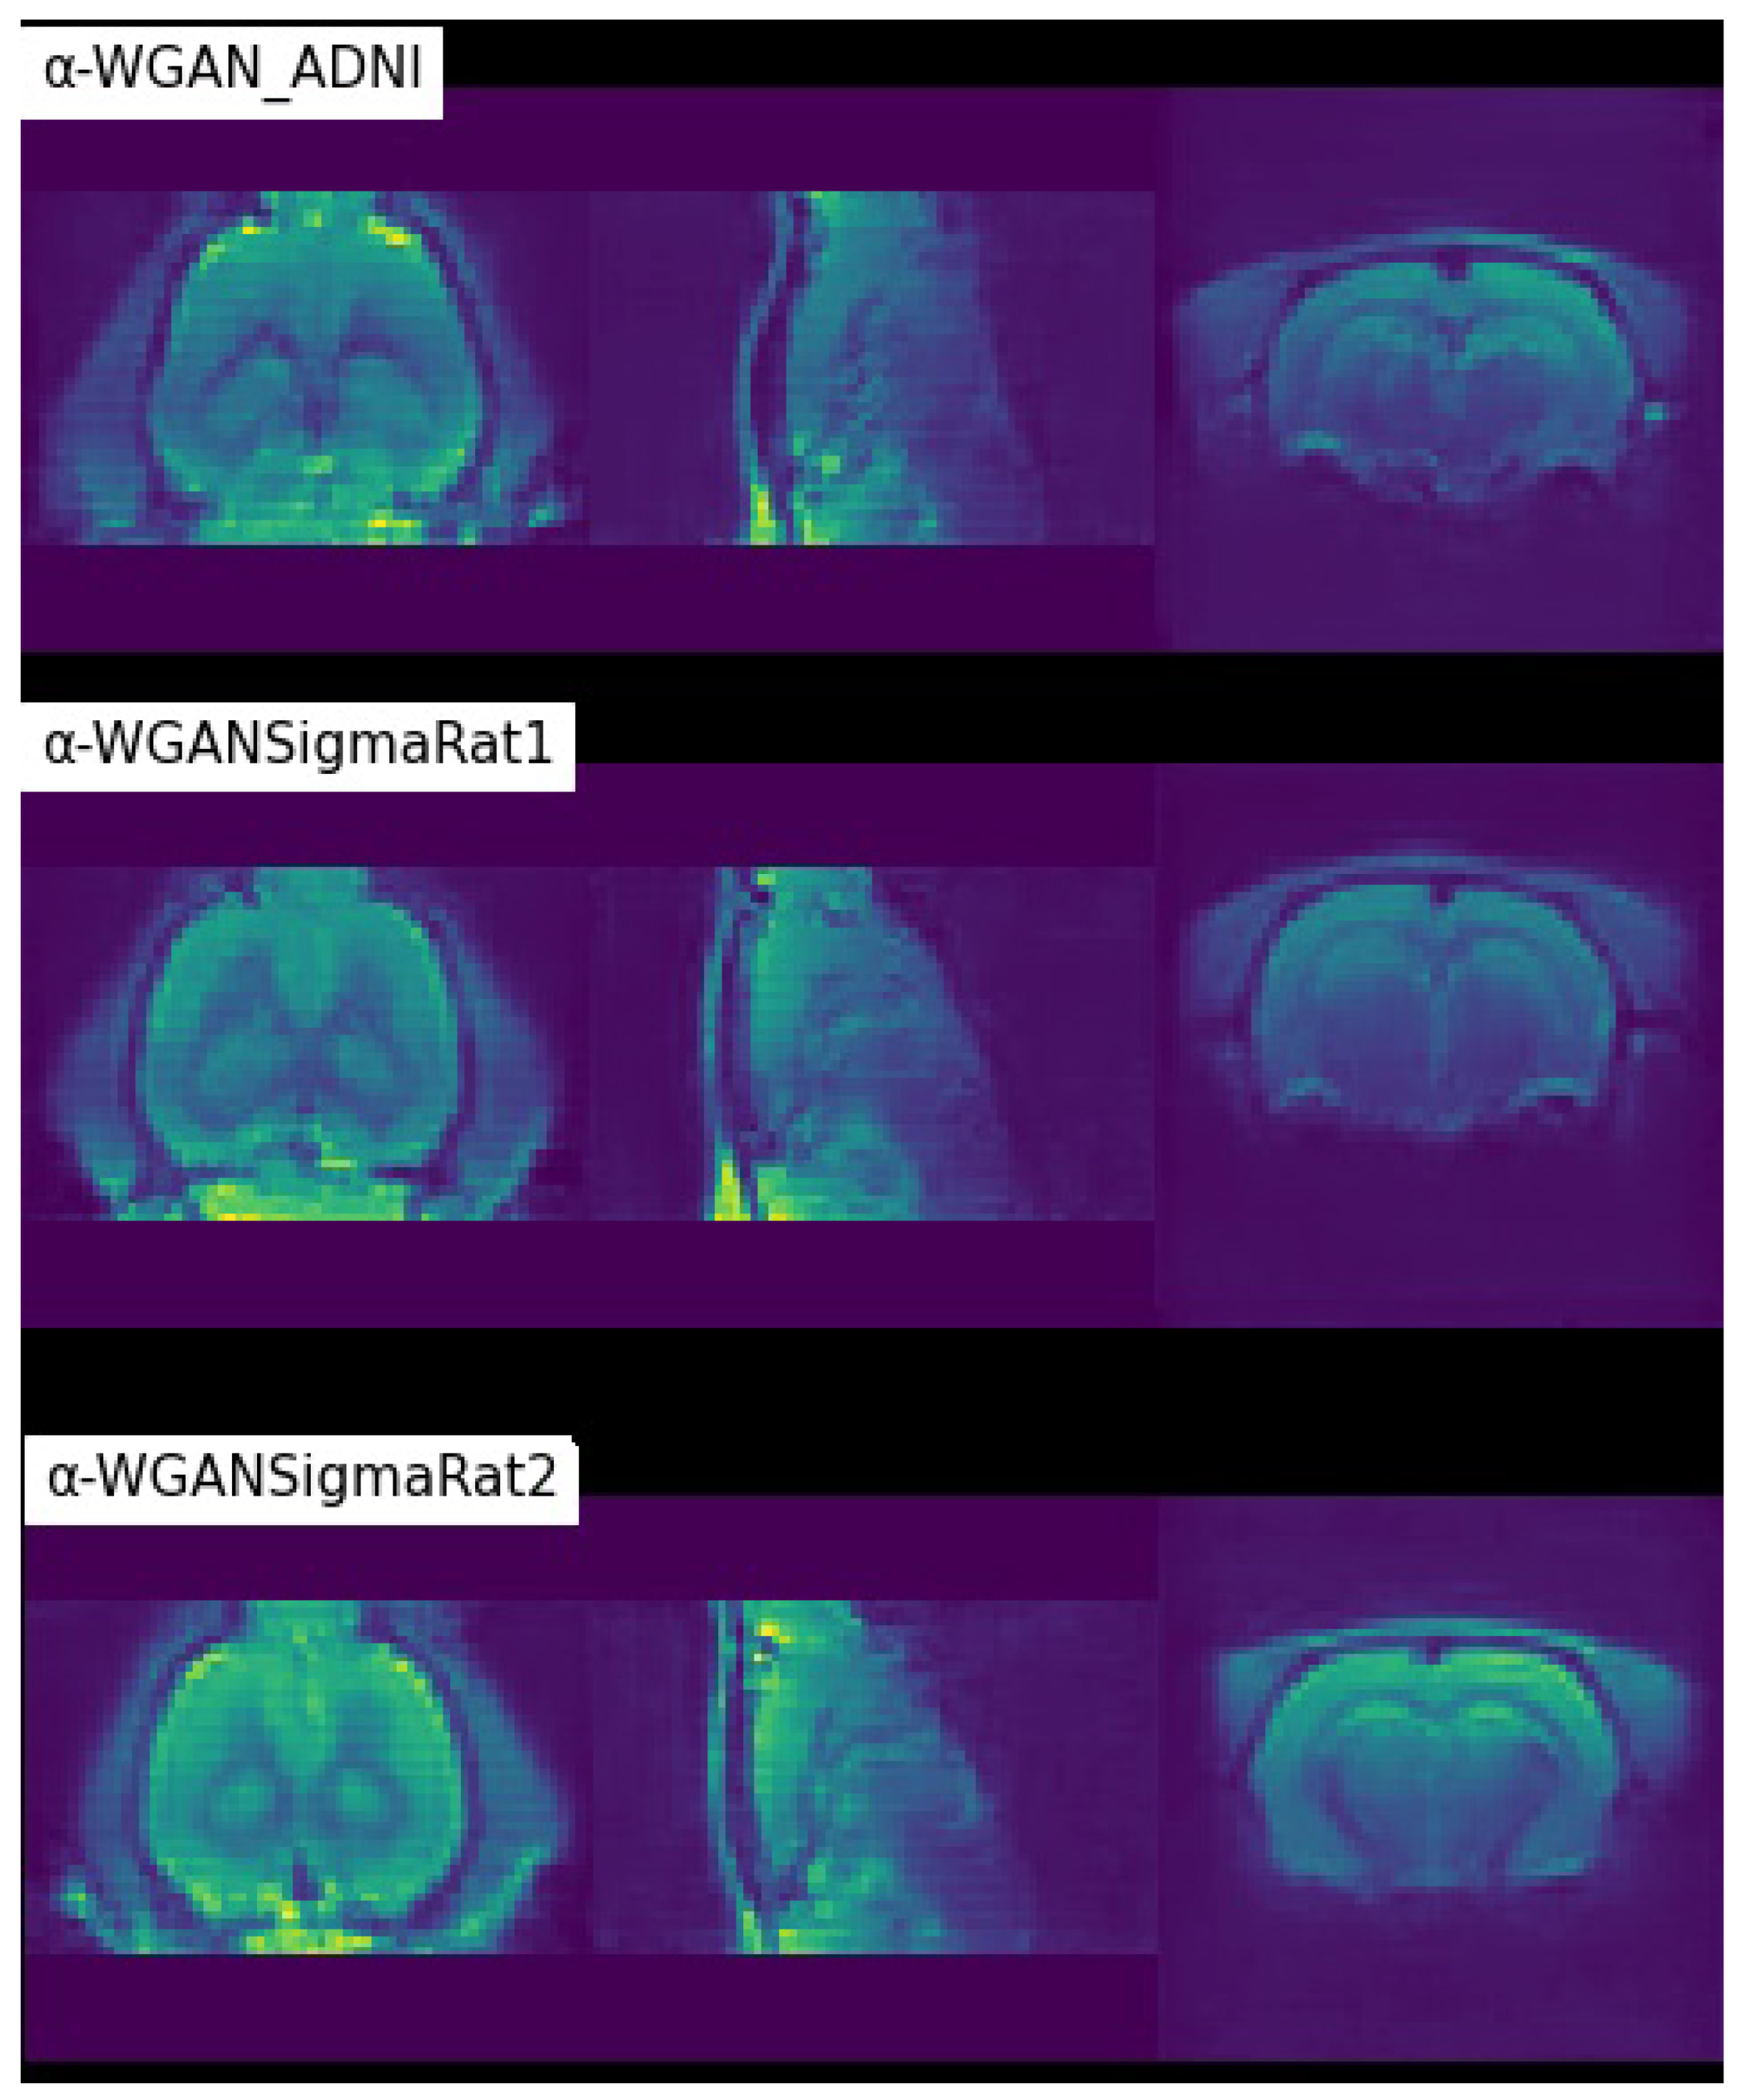

From Table 2, it can be seen that the new models outperformed the baseline model in all quantitative metrics. The -WGANSigmaRat1 had the best overall quantitative results, but after a quick analysis of several scans by some specialists and the authors, the -WGANSigmaRat2 model seems to produce more realistic scans with less blur and fewer structural anomalies, as shown in Figure 7. Therefore, these two models were used for the Turing test. The -WGAN_ADNI model was discarded for the Turing test because it was too easy to distinguish between real and generated scans. This architecture, adapted from [26], was unable to properly learn the distribution of the dataset, and the generated scans contain artefacts, as seen in Figure 7.

Figure 7.

Coloured visualisation of scans generated by different models in the coronal, sagittal and axial planes, respectively.